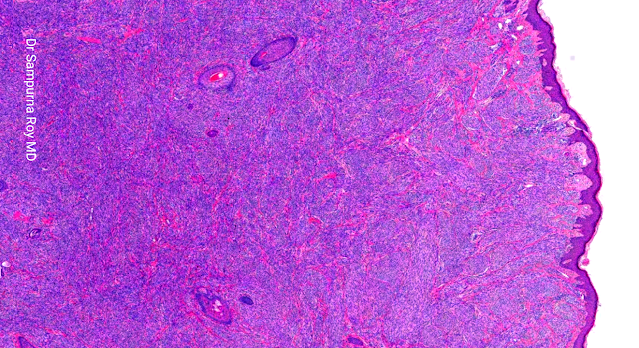

Dermatopathology Case 202

45-year-old female who presented with a slow-growing painless swelling over the back of the thigh that had been present for 4 years. Answer

Self Assessment Cases in Dermatopathology: Editor: Dr Sampurna Roy MD INDIA